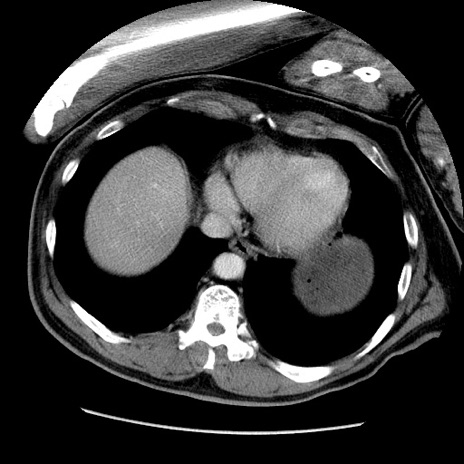

症例22(横断像)

【症例】50歳代男性

【主訴】腹痛

【現病歴】AVMからの被殻出血のため回復期リハ病棟入院中。 本日午後3時頃急に下腹部痛が出現した。

【既往歴】AVM、被殻出血、虫垂炎、高血圧

【身体所見】意識晴明、左半身不全麻痺、会話の理解は良好、36.5°C、腹部:膨隆、全体に板状硬、下腹部正中に圧痛点あり、反跳痛-、筋性防御不明、右下腹部にope scar

【データ】WBC 9400、CRP 0.06